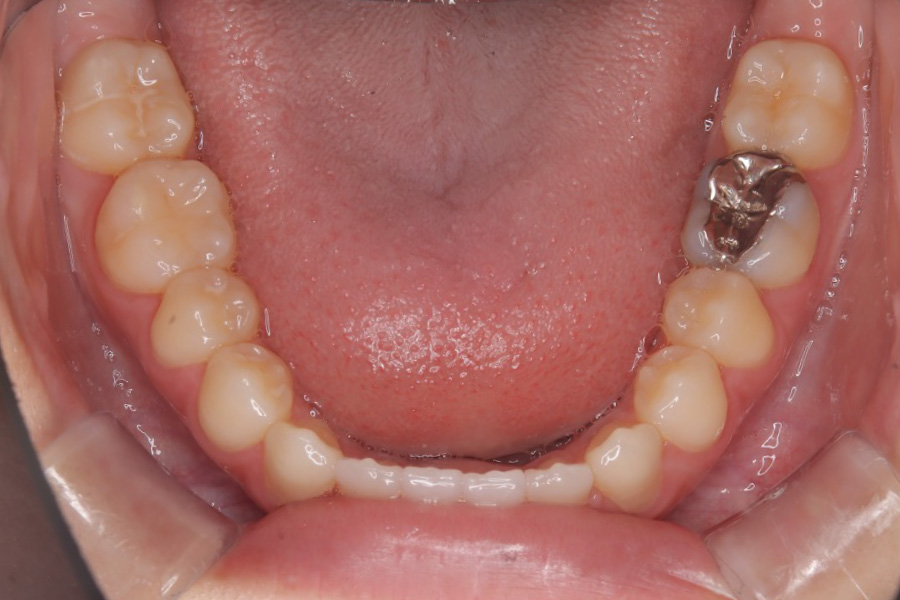

治療前

主訴 前歯で噛めない

治療内容 インビザライン矯正

非抜歯